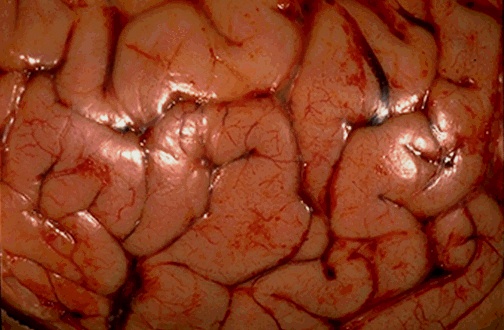

The surface of the brain with cerebral edema demonstrates widened gyri with a flattened surface. The sulci are narrowed.